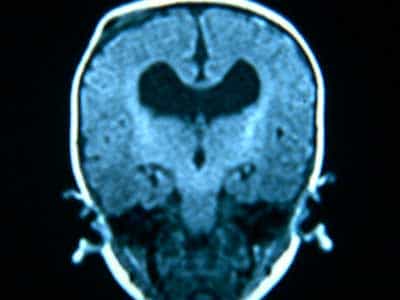

AGENESIA DEL CUERPO CALLOSO: los axones que deberían haber cruzado a través del cuerpo calloso se disponen formando haces longitudinales en la cara interna de los hemisferios cerebrales. El sistema ventricular esta dilatado y a veces hay quistes interhemisféricos. Puede asociarse con otras malformaciones.(Fig. 12)